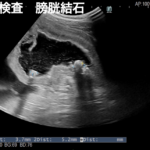

食欲不振、元気消失、嘔吐を主訴に動物病院を受診し、腹水貯留の精査のためCT撮影、導尿処置によって尿道閉塞による膀胱破裂と診断されました。